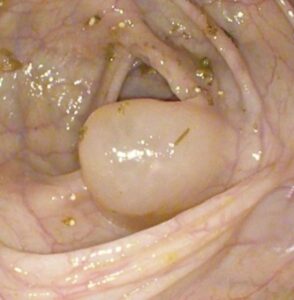

Атлас

В эндоскопическом атласе обычно представлены изображения и видео, полученные во время процедур, проводимых врачами-эндоскопистами. Эти изображения и видео могут использоваться для обучения студентов медицинских учебных заведений, повышения квалификации медицинских работников, а также для консультации врачей при диагностике и лечении различных заболеваний.